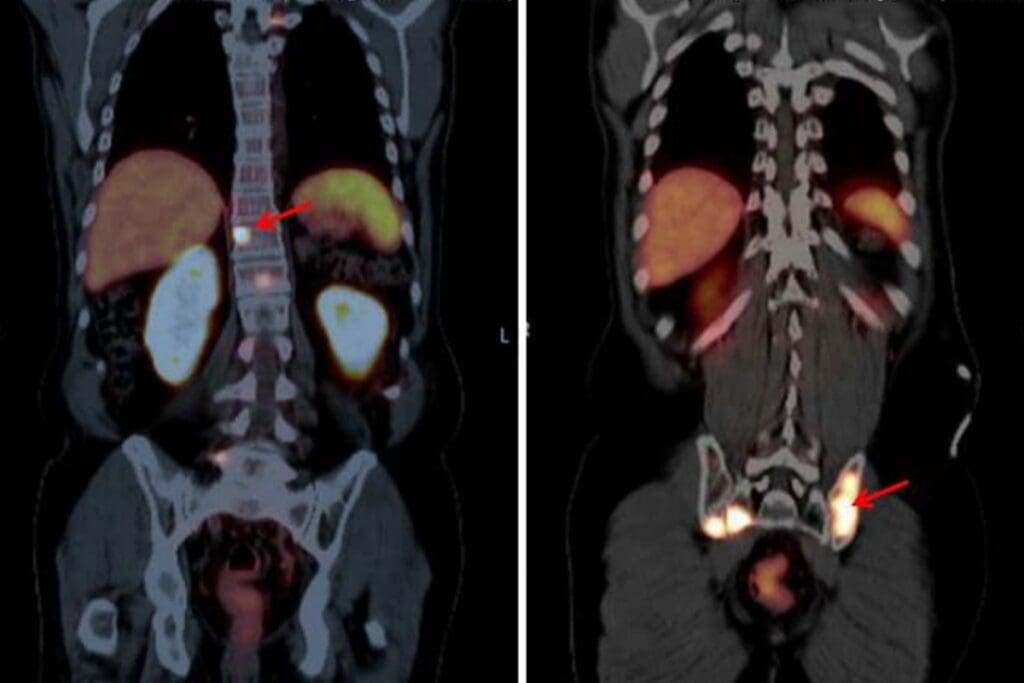

Nephrographic Phase: Kidney Parenchyma Evaluation

Next, contrast material is given, and images are taken. This is the nephrographic phase. It happens when the contrast is absorbed by the kidney, about 90-100 seconds after.

This phase is great for checking the kidney parenchyma. It helps find tumors or other problems in the kidney tissue.

Excretory Phase: Collecting System Assessment

The last phase is the excretory phase. It happens when the contrast is being passed into the kidneys’ collecting system. Images from this phase, about 5-10 minutes after, show the renal pelvis, ureters, and bladder well.

This phase is vital for the collecting system. It helps spot tumors, strictures, or blockages in the urinary tract.

By looking at all three phases, we get a full picture of the urinary tract. This improves diagnosis and helps choose the right treatment.